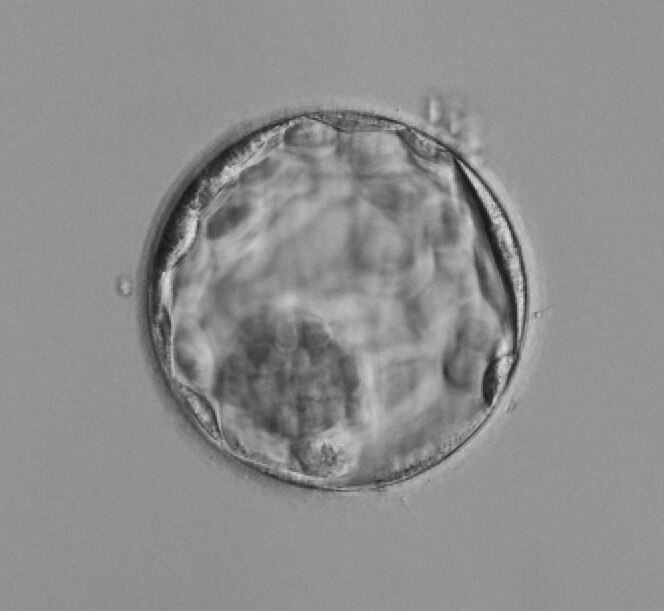

Efter ungefär 4 dagar når embryot, som nu kallas morula, fram till livmoderhålan. Här utvecklas embryot till en blastocyst under 5:e dagen, vilket innebär att två typer av celler bildats – inre cellmassan som kommer bilda själva fostret, samt ett yttre cellager som kommer bilda moderkaka och fosterhinnor. Runt embryot finns ett skyddande skal som embryot nu tar sig ut igenom för att implantera, vilket innebär att fästa in i livmoderns slemhinna. I samband med implantationen kan kvinnan märka av en lite blödning, vilken är helt ofarlig.